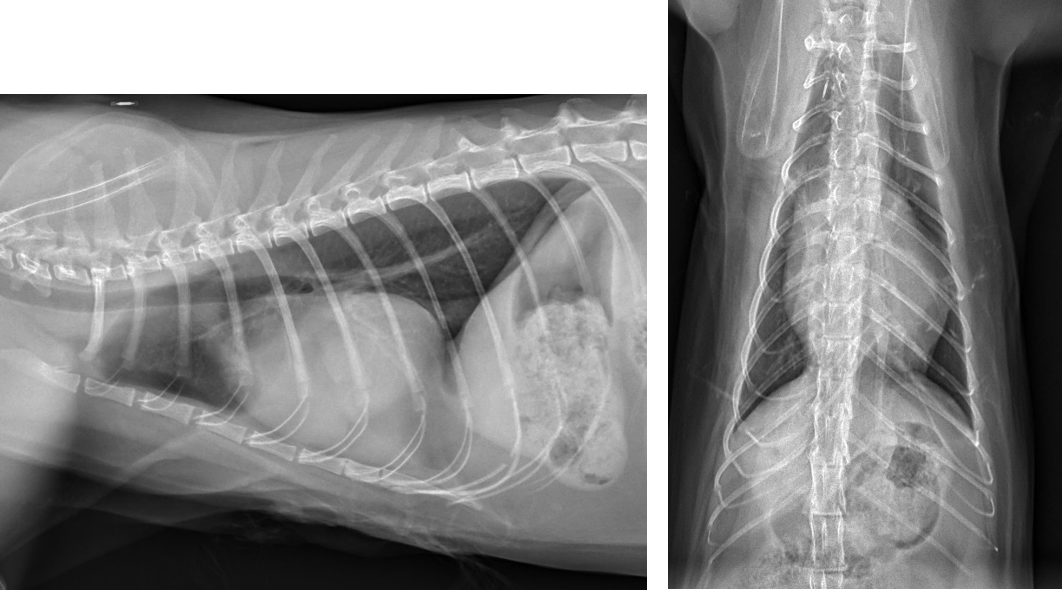

There are several congenital diseases of the pericardium recognized in small animals. Although peritoneopericardial diaphragmatic hernias (PPDH) are the most common type of congenital abnormality encountered (Figure 1), sporadic reports of partial pericardial defects and intrapericardial cysts have been published.2

Thoracic radiography usually demonstrates abnormalities when there is significant accumulation of pericardial fluid. The cardiac silhouette loses its angles and waists and becomes globe-shaped (Figure 3). Most cases are not "classic" and require integration with the other data. Pulmonary vascularity is often reduced from low cardiac output in contrast to congestive heart failure (CHF) from cardiomyopathy or valvular disease in which the pulmonary vascularity may be increased (especially the pulmonary veins).